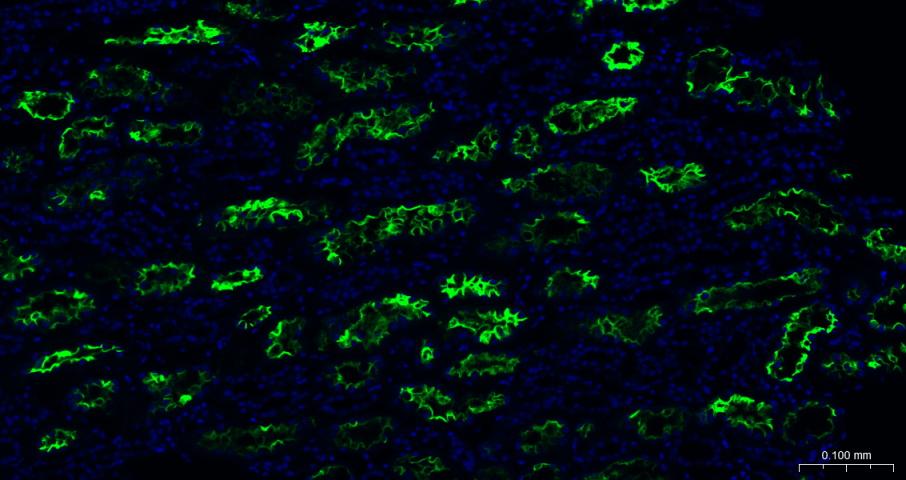

| IHC-P | Human, Mouse, Rat | 1:100-500 | |

| IHC-F | Human, Mouse, Rat | 1:100-500 | |

| IF | Human, Mouse | Rat | 1:100-500 |

| ICC/IF | Human, Mouse, Rat | 1:50-200 |

Expressed in endothelial cells from small and large arteries, and in arterial smooth muscle cells (at protein level) (PubMed:15141377).

Expressed in enterocytes of the small intestine, Leydig cells and Sertoli cells (at protein level) (PubMed:15141377).

Expressed in the renal proximal tubule and the small intestine (at protein level) (PubMed:18424768).

Expressed in heart, kidney, testis, and gastrointestinal system (at protein level) (PubMed:10969042, PubMed:10924499, PubMed:15231706, PubMed:12459472, PubMed:15671045, PubMed:32715618, PubMed:32170560).

In lung, expressed at low levels in some alveolar type 2 cells, the expression seems to be individual-specific (at protein level) (PubMed:32425701, PubMed:15141377, PubMed:32715618, PubMed:32170560, PubMed:33432184).